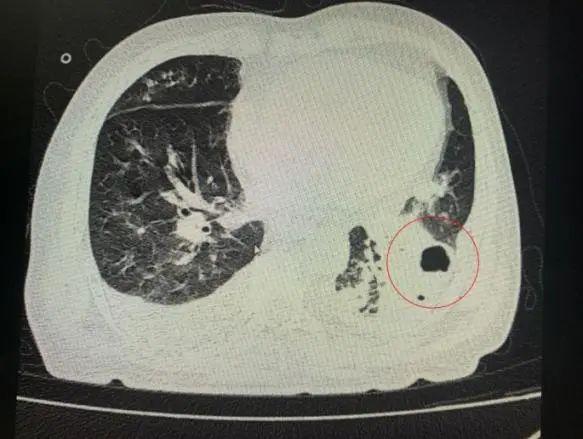

番禺院區(qū)呼吸內(nèi)科何夢(mèng)璋主任接診后,對(duì)鐘叔進(jìn)行詳細(xì)檢查。此時(shí),鐘叔的病情已經(jīng)十分危急,由于不能自主呼吸,他帶上了呼吸機(jī)輔助呼吸調(diào)節(jié)。看到鐘叔胸片時(shí),醫(yī)護(hù)人員頭皮也一陣發(fā)麻,胸部CT可見(jiàn)雙肺多發(fā)的炎癥浸潤(rùn)、雙肺多發(fā)空洞。通俗來(lái)說(shuō),鐘叔的肺部已經(jīng)被病原體蠶食,啃出個(gè)大小各異的洞!可怕的是,這種病變對(duì)肺功能的破壞是性、不可恢復(fù)的。根據(jù)鐘叔病史以及胸部CT結(jié)果,終診斷為“吸入性肺膿腫”。

鐘叔的肺部被病原體蠶食,啃出個(gè)大小各異的洞。